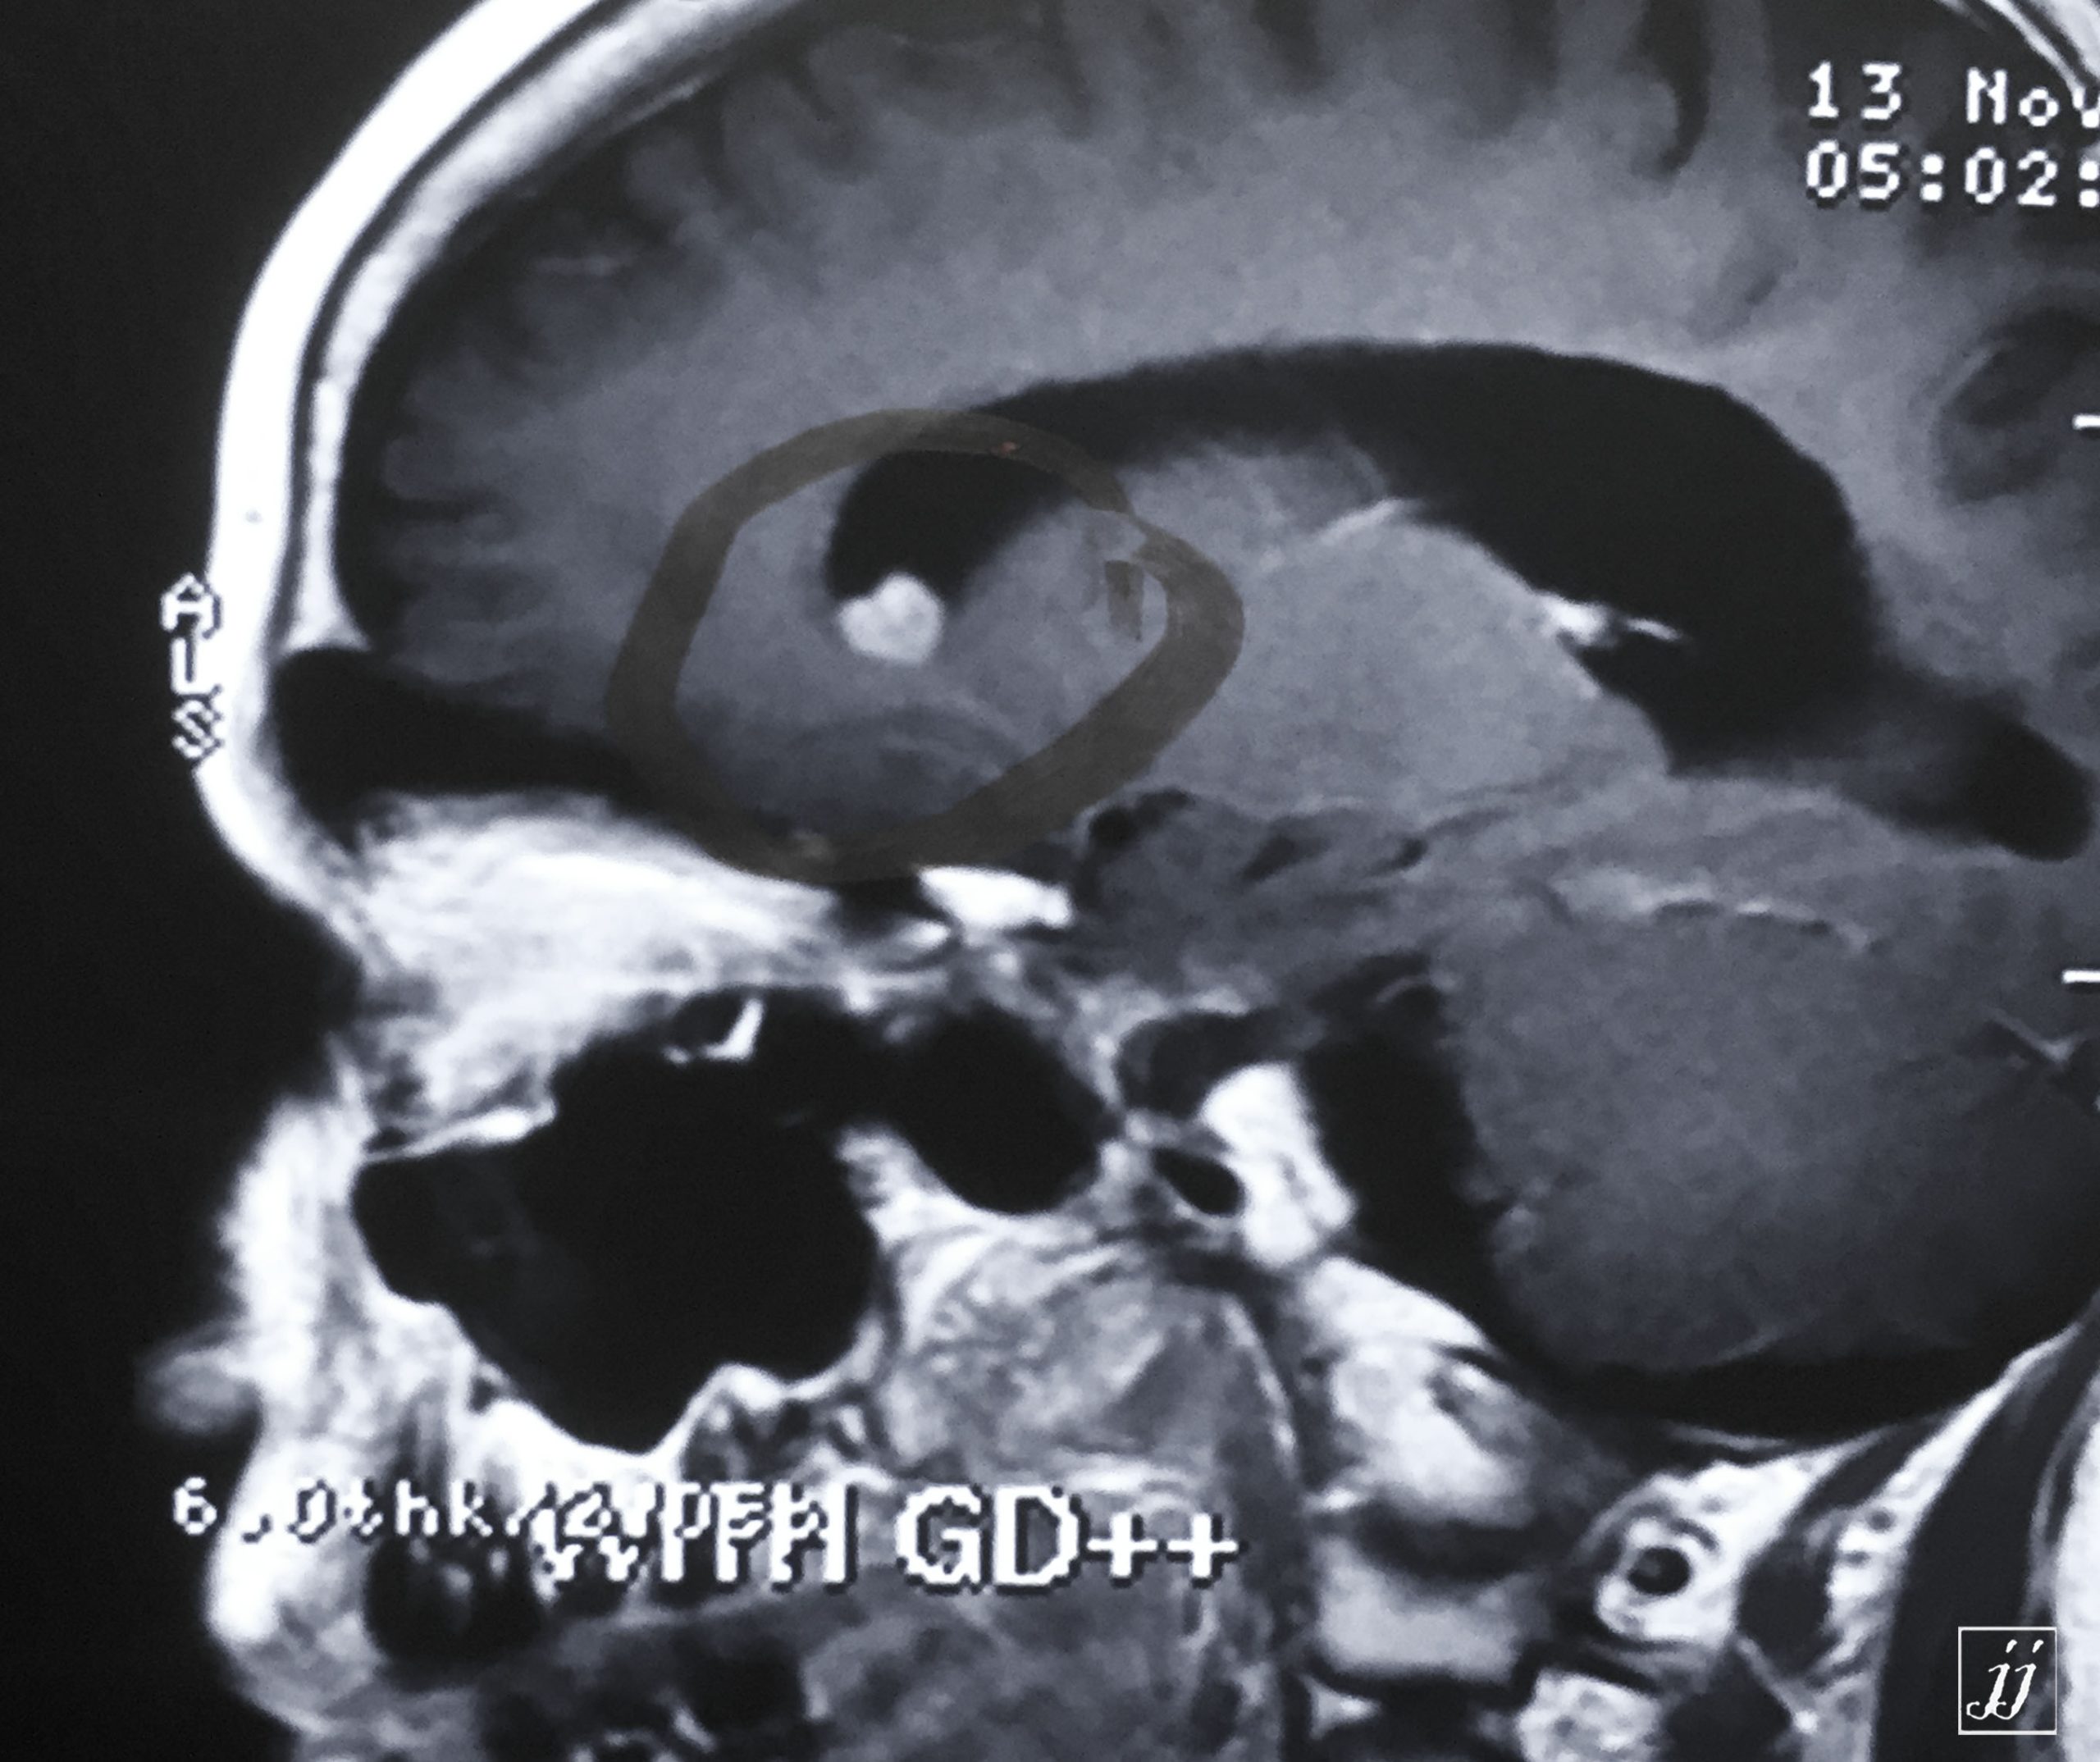

Hypophysis- a plaque of corpus callosum genum enhancement (3)